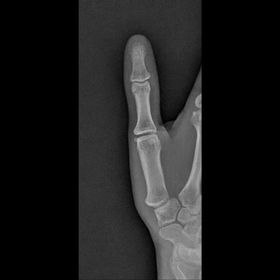

| Oblique Digit | finger not parallel to IR *should be more concave to one side* |

| Oblique Digit | finger not obliqued to 45 degrees - can't see the concavity of one side of the digit joint spaces closed |

| Lateral Digit | finger bent back - not truly lateral |

| Lateral Digit | artifact |

| What's the evaluation criteria for the PA Finger X-Ray? | ANATOMY: distal phalynx -> distal 1/2 of metacarpal demonstrated CRITERIA: - equal concavity on both sides of phalanges - IP and MCP open - no overlapping of adjacent fingers POSITIONING: CR perpendicular @ PIP joint |

| What's the evaluation criteria for the Lateral finger x-ray? | ANATOMY: entire digit demonstrated CRITERIA: open joint spaces concave to one side, while the dorsal side is straight no overlapping of adjacent fingers/soft tissues POSITIONING: CR perpendicular @ PIP joint |

| Oblique finger x-ray image criteria? | ANATOMY: entire digit demonstrated CRITERIA: more concavity to one side open joint spaces no superimposition of adjacent fingers POSITIONING: CR perpendicular @ PIP joint |